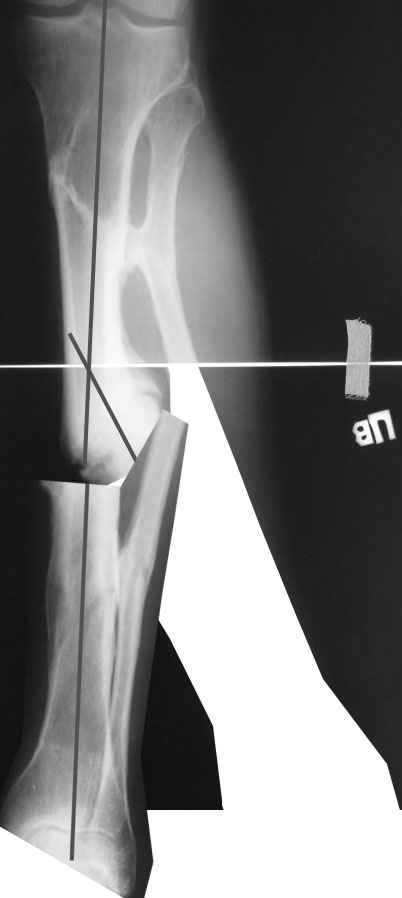

Одномоментно такой угол устранить трудно, сильно натянутся ткани по

наружной поверхности голени. Может и стопа повиснуть. А что по второй

проекции?

Мы бы сделали после остеотомии малоберцовой и аппаратной коррекции.

Большеберцовую можно исправить за счет растяжения пседартроза. Можно

и сделать поперечную остеотомию чуть дистальнее несращения, в этом

случае будет удобный вход в периферический отломок. А зону несращения

пройти разверткой просто по прямой. Схема в приложении.